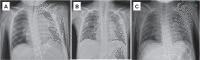

Figure 1.

Intermittent treatment response of the mediastinal tumor mass on crizotinib, as seen on chest x-ray. A) Apical (AP) chest x-ray before administration of crizotinib; B) Stable disease after 7 days of daily crizotinib (oral capsules) on AP chest x-ray; C) Improved anti-tumor effect on day 28 after 14 days of crizotinib via nasogastric tube and intravenous vinblastine.